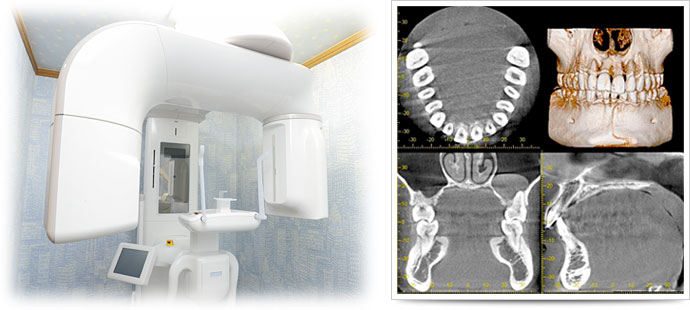

歯や顎の構造を分析 -「CT(3次元立体画像)」

人によっての歯や顎の構造は異なります。これらの構造を把握するために多くの歯科医院がレントゲン撮影を試みるのですが、レントゲンでは平面としてしか捉えることができないため、正確に構造を知ることは極めて困難だと言えます。

歯科用CT(3次元立体画像)を利用することで、レントゲンでは見えない部分も可視化することができ、より一層精密な診査・診断、そして治療が可能になります。当然、咬み合わせを考慮する際もプラスの効果を発揮します。